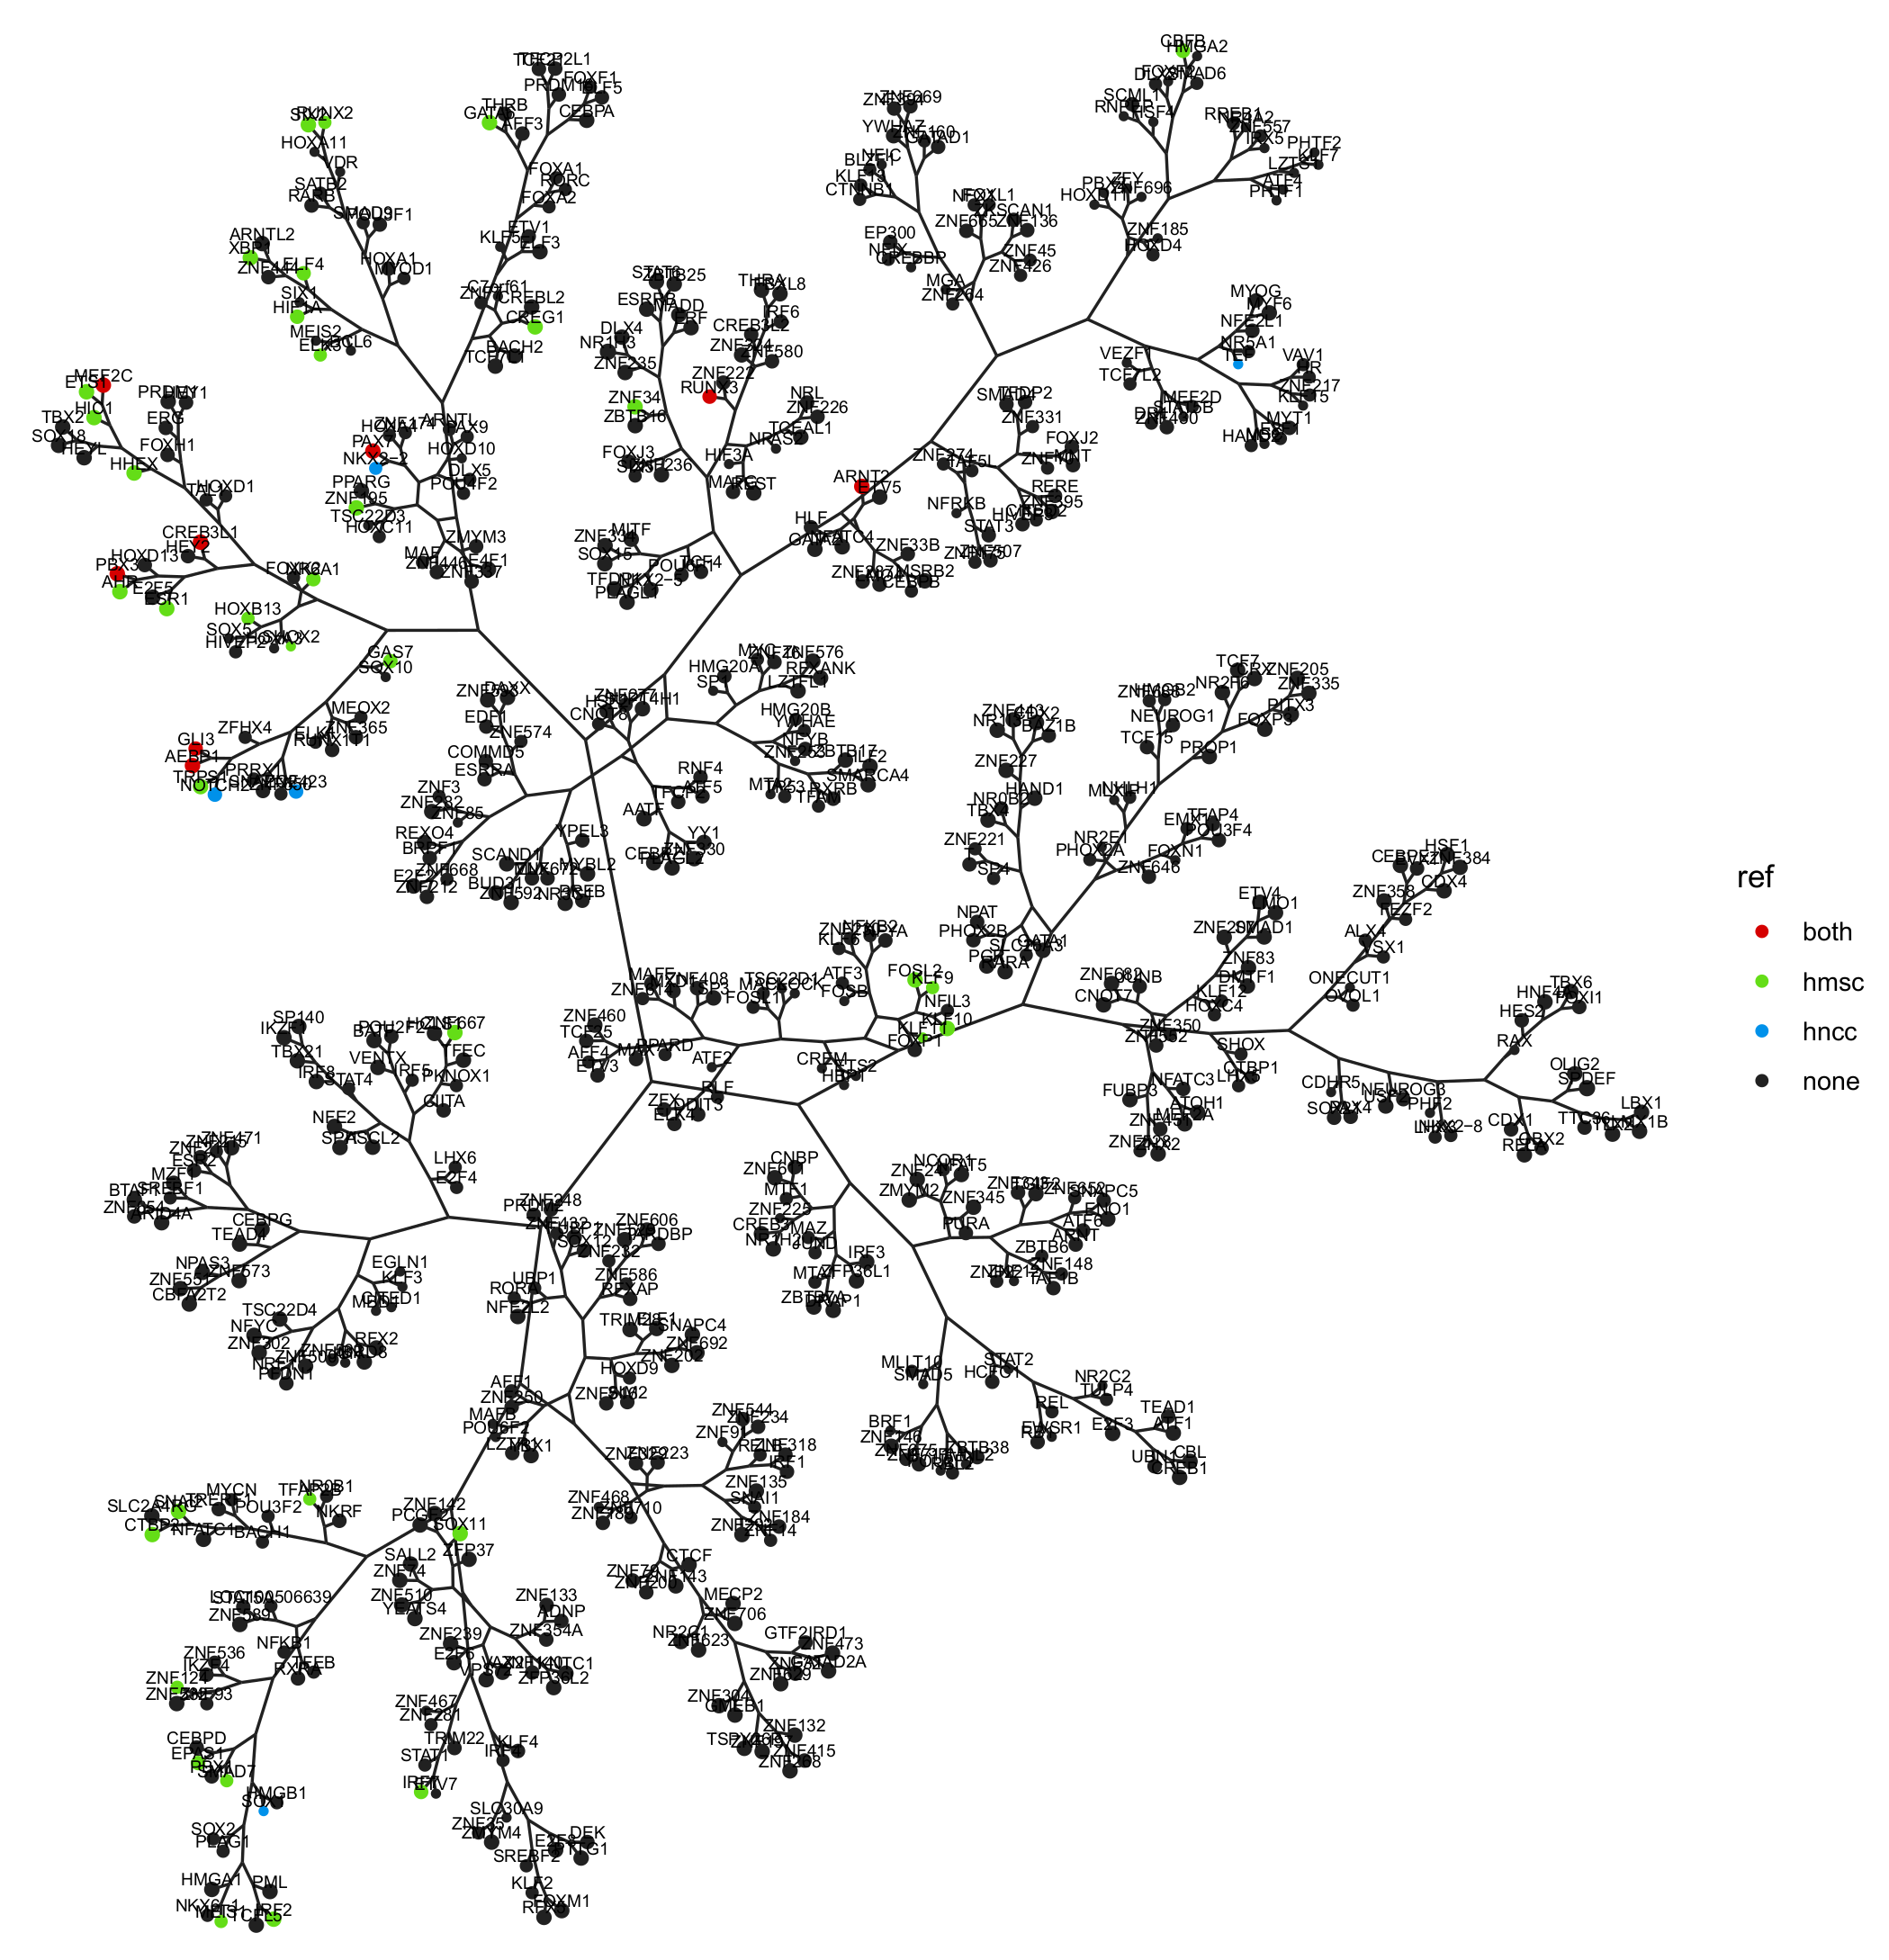

3.1. Regulatory Network Inference and Master Regulator Analysis